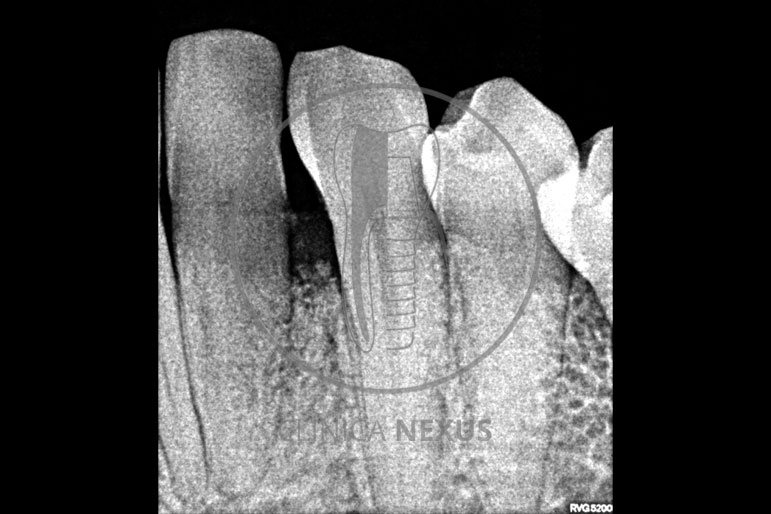

Tratamiento de defectos periodontales infraóseos en sector antero-inferior empleando gel de amelogeninas (Emdogain®) en combinación con un aloinjerto óseo (Biobank®). Paciente de 64 años, sin problemas médicos de relevancia, que presenta una periodontitis leve generalizada, pero asociada a presencia de defectos óseos verticales profundos a nivel de los espacios interdentales entre los caninos y los incisivos laterales inferiores. Tras la pertinente fase higiénica, se llevó a cabo una cirugía periodontal regenerativa, en la que, tras eliminar el cálculo subgingival (factor causal), se empleó una combinación de amelogeninas con un aloinjerto, para promover la regeneración tisular del periodonto perdido. Las imágenes clínicas y radiológicas, al año de seguimiento, reflejan un resultado terapéutico óptimo, con regeneración completa del tejido periodontal y mejora del pronóstico de los dientes involucrados.